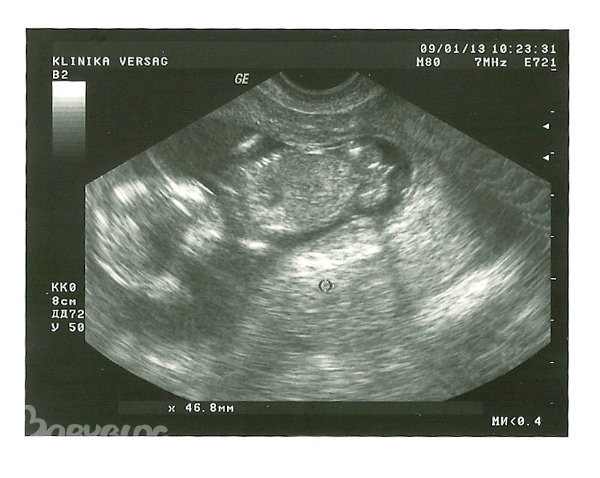

УЗИ 1 скрининга 13 недель

Результаты: УЗИ, КТГ, доплера, скринингаПриветики, девочки! Была сегодня на УЗИ первого скрининга, делала в платной клинике, в моей ЖК на январь мест нет. Врач все подробно рассказала, у нас все хорошо - и пальчики видели и все ручки-ножки, слушали сердечко, показали желудок и мочевой пузырь. По М срок 12нед и 7дн, по УЗИ на 2 дня больше ))))) КТР 62мм, БПР 25мм, ТВП 1,4мм, носовая косточка есть, даже на фото в профиль видно. Врач смотрела долго, малыш активный, долго крутился, хотела сфотографировать красиво, сказала, скорее всего мальчик, между ножек точно что-то есть ))))) посмотрите на фото, может тоже кто-то разглядит мужскую писюльку ))) у нас с мужем радости полные штаны

поздравляю)) такое чувство на первом фото он ножки назад загнул, как будто на коленках сидит и между ножек правда что то есть)))))